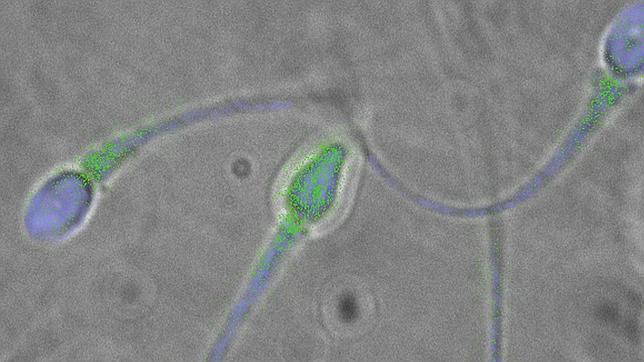

Los espermatozoides humanos son nadadores ciegos capaces de nadar en la dirección adecuada y recorrer una ... distancia que puede ser más de 1.000 veces su longitud. ¿Cómo es posible? Pues, según un grupo de investigadores de la Universidad de Cambridge ha publicado un estudio en la revista «eLife» , lo hacen jugando en equipo y guiándose por la corriente que se forma en las trompas de Falopio, donde han de encontrarse con el óvulo.

«Descubrimos que si creas las corrientes adecuadas, puedes observarles nadando a contracorriente durante muchos minutos», dijo Jörn Dunkel para la agencia UPI. Su equipo ha diseñado unos «micro-tubos» para observar cómo se mueven los espermatozoides en su interior. «Casi siempre se acumulan en la superficie de los tubos, y dada la elevada concentración local de estas células, podría haber una cooperación entre los espermatozoides que les permitiera nadar más rápido en grupo».

Los investigadores han descubierto además que los espermatozoides no nadan en línea recta, sino que trazan espirales a lo largo de las paredes de los tubos, probablemente para evitar el centro de los conductos, donde la velocidad de la corriente es mayor.

Para averiguarlo, investigaron los movimientos de espermatozoides de humanos y toros en varias condiciones fisiológicas y de viscosidad. Según sus resultados, la asimetría de los movimientos del flagelo, la cola que los espermatozoides usan para propulsarse, es un mecanismo de rectificación de la dirección de natación, para asegurarse de llegar al óvulo.